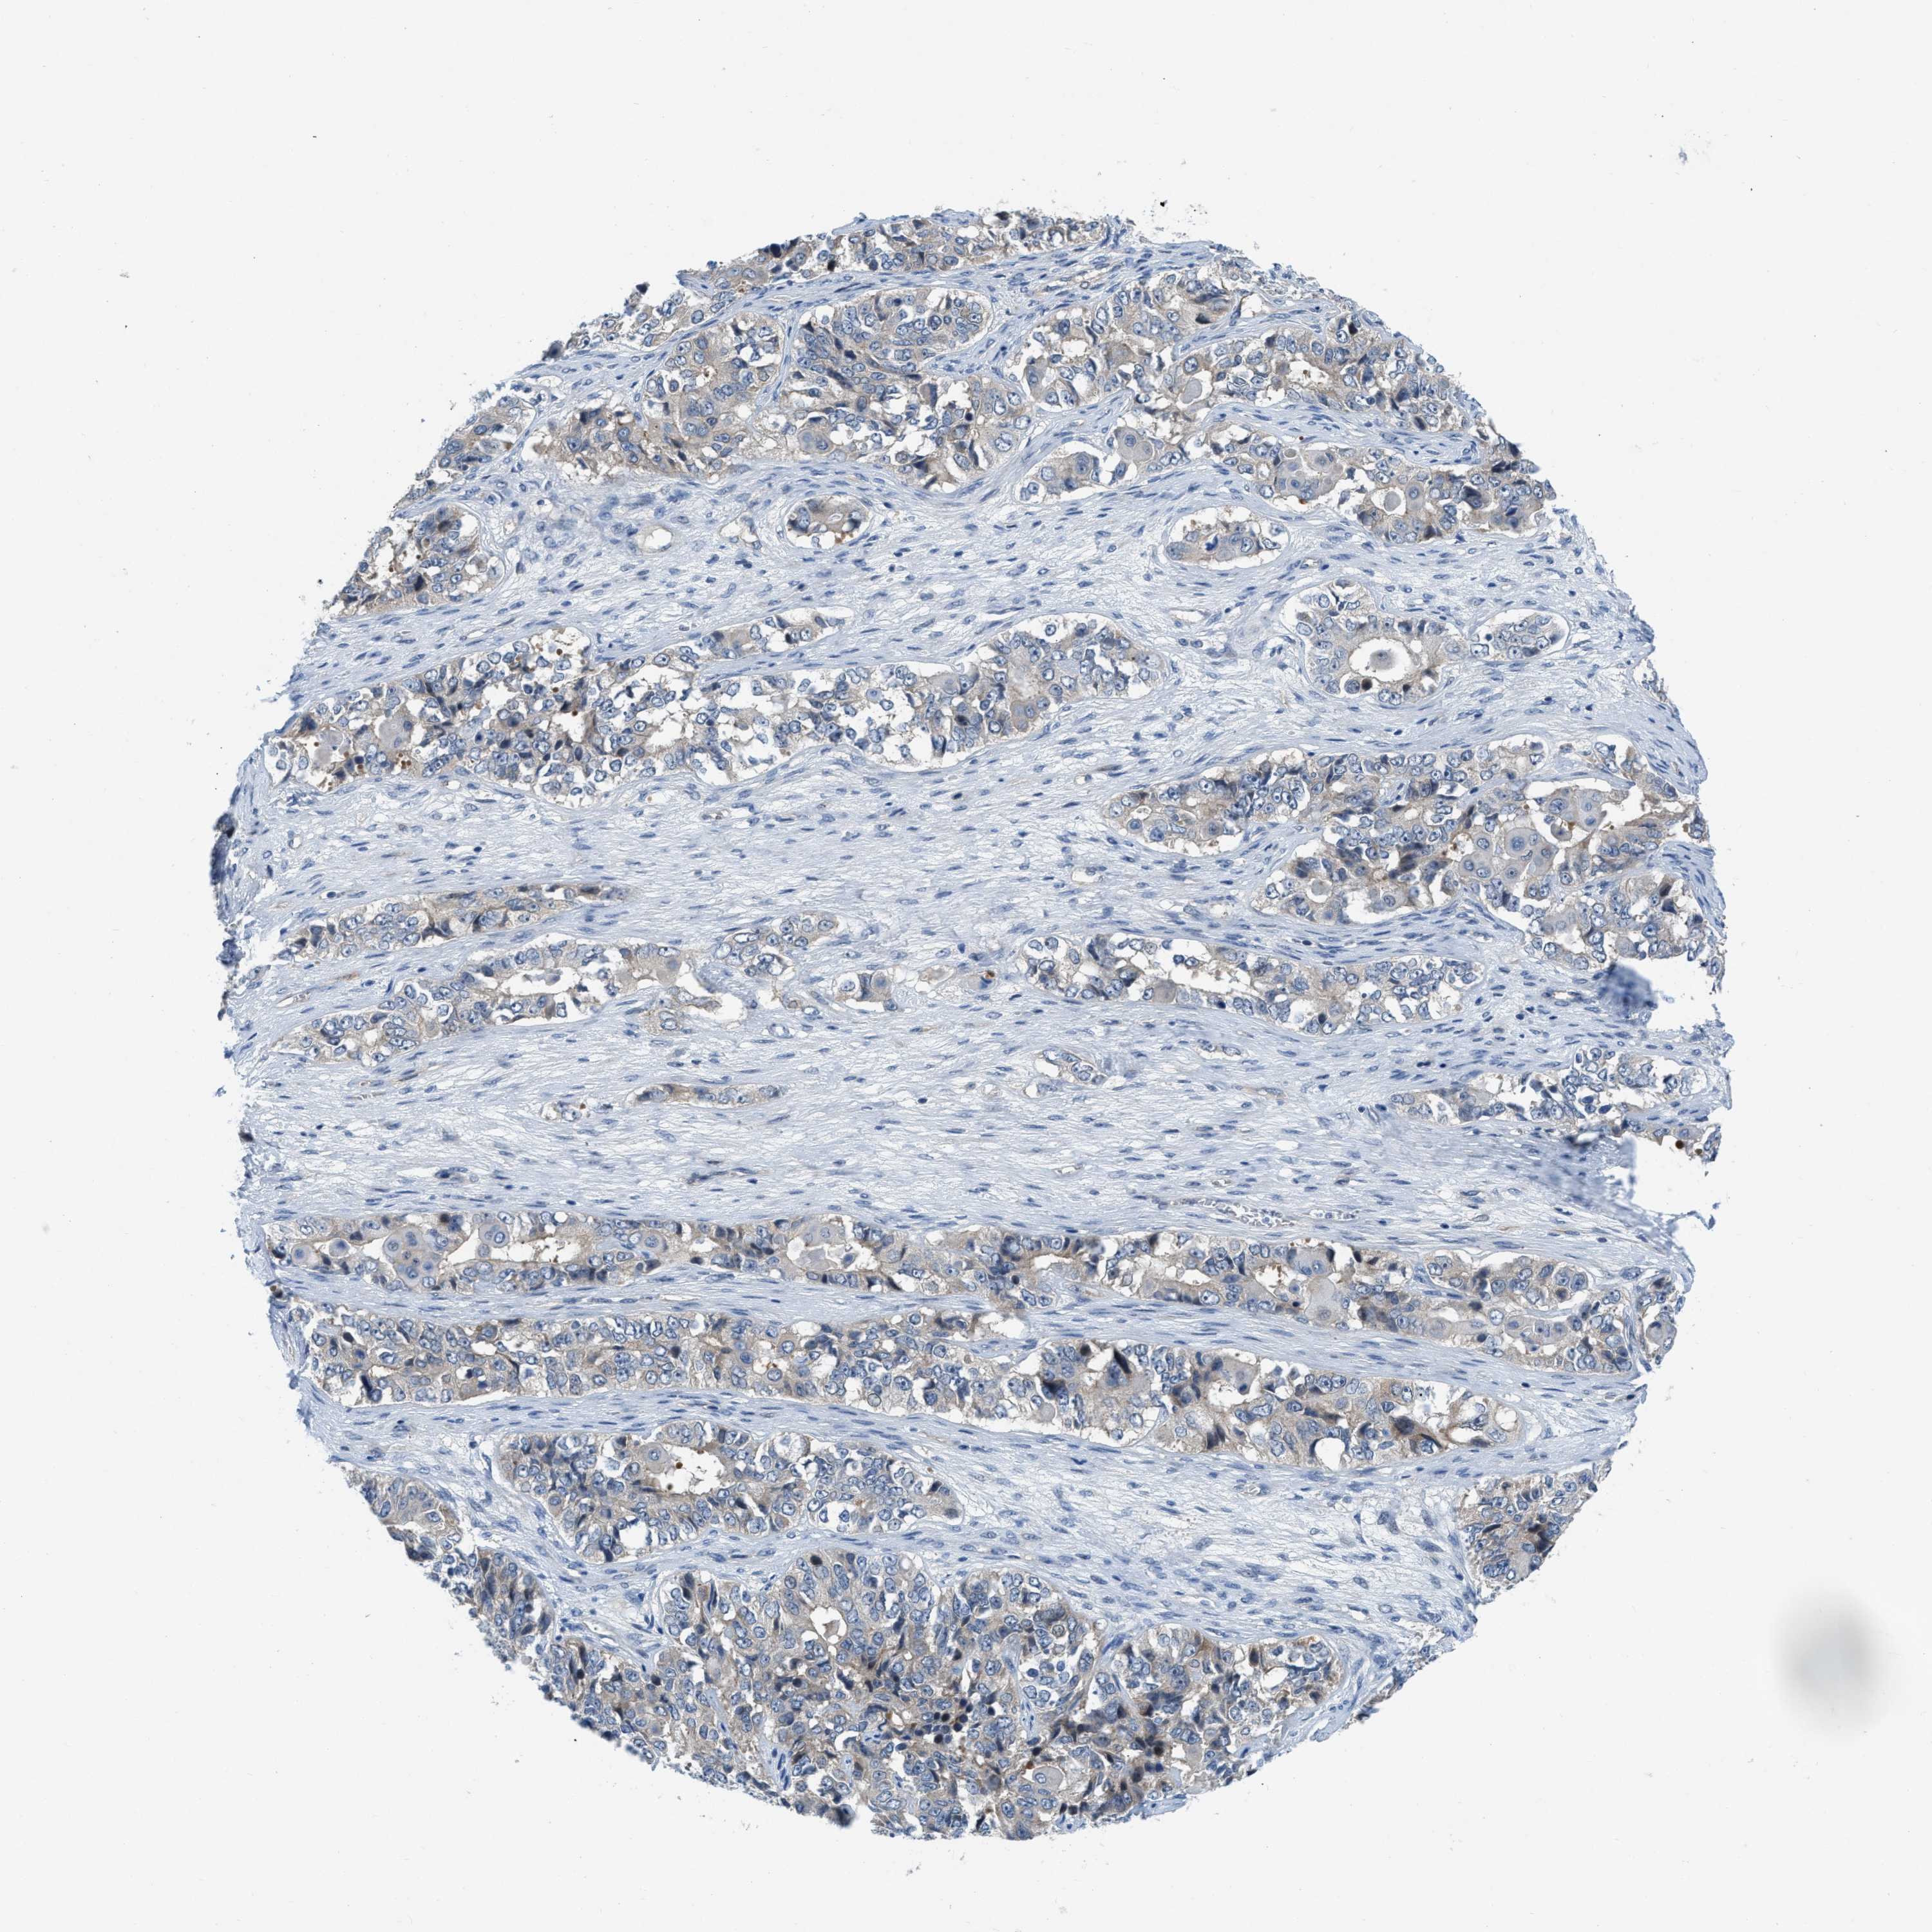

OVARIAN CANCER - Protein expressioni

A mouse-over function shows sample information and annotation data. Click on an image to view it in a full screen mode. Samples can be filtered based on level of antibody staining by selecting one or several of the following categories: high, medium, low and not detected. The assay and annotation is described here.

Note that samples used for immunohistochemistry by the Human Protein Atlas do not correspond to samples in the TCGA dataset.

Antibody stainingi

Antibody staining in the annotated cell types in the current human tissue is reported as not detected, low, medium, or high, based on conventional immunohistochemistry profiling in selected tissues. This score is based on the combination of the staining intensity and fraction of stained cells.

Each image is clickable and will lead to virtual microscopy that enables deeper exploration of all samples and also displays staining intensity scores, fraction scores and subcellular localization as well as patient and tissue information for each sample.

Antibody HPA018257

Staining

High

Medium

Low

Not detected

Intensity

Strong

Moderate

Weak

Negative

Quantity

>75%

75%-25%

<25%

None

Location

Nuclear

Cytoplasmic/membranous

Cytoplasmic/membranous,nuclear

Cystadenocarcinoma, serous, NOS

Carcinoma, endometroid

Cystadenocarcinoma, mucinous, NOS

Carcinoma, NOS